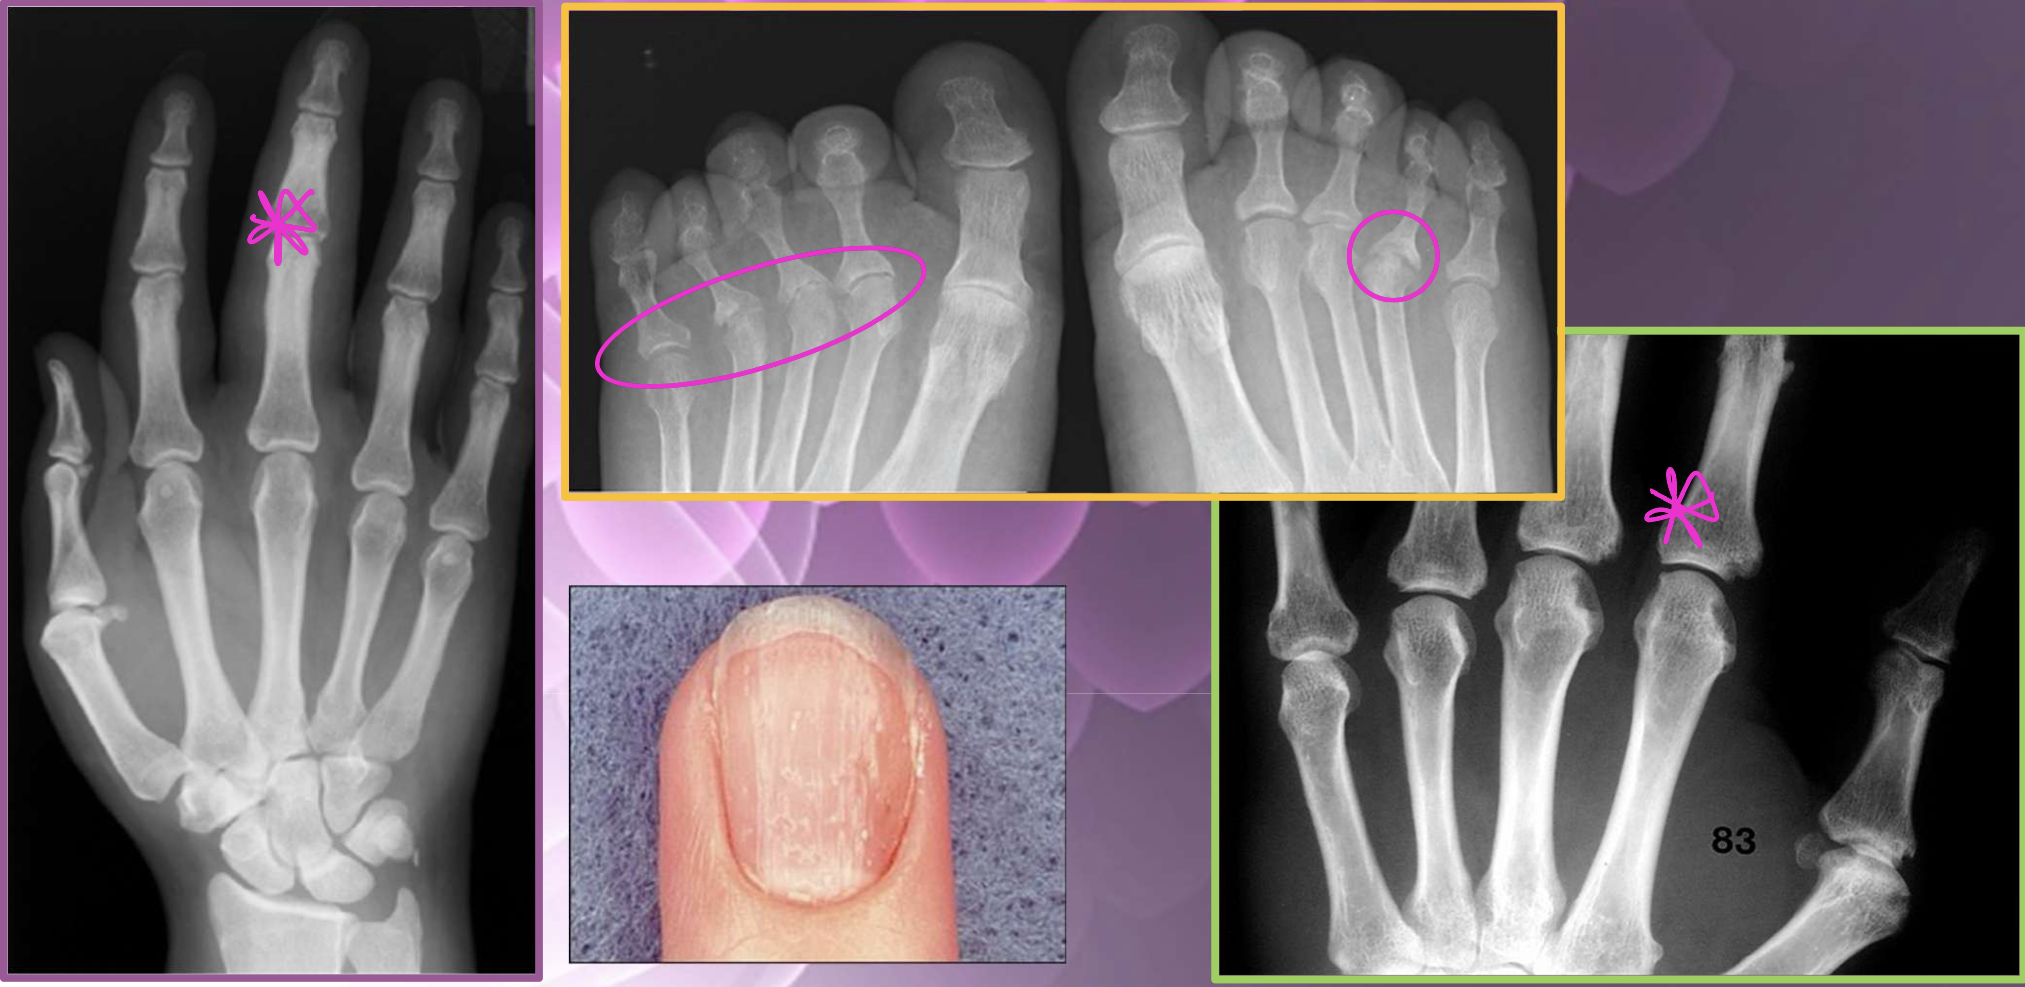

What type of characterisitcs of PsA are found in this image

soft tissue edema

nail pitting

JSN + central erosions (pencil in cup)

periostitis (lifted periosteum - mouse ears)

What are the two dx of these images (left vs right)

Left = PsA

Right = AS